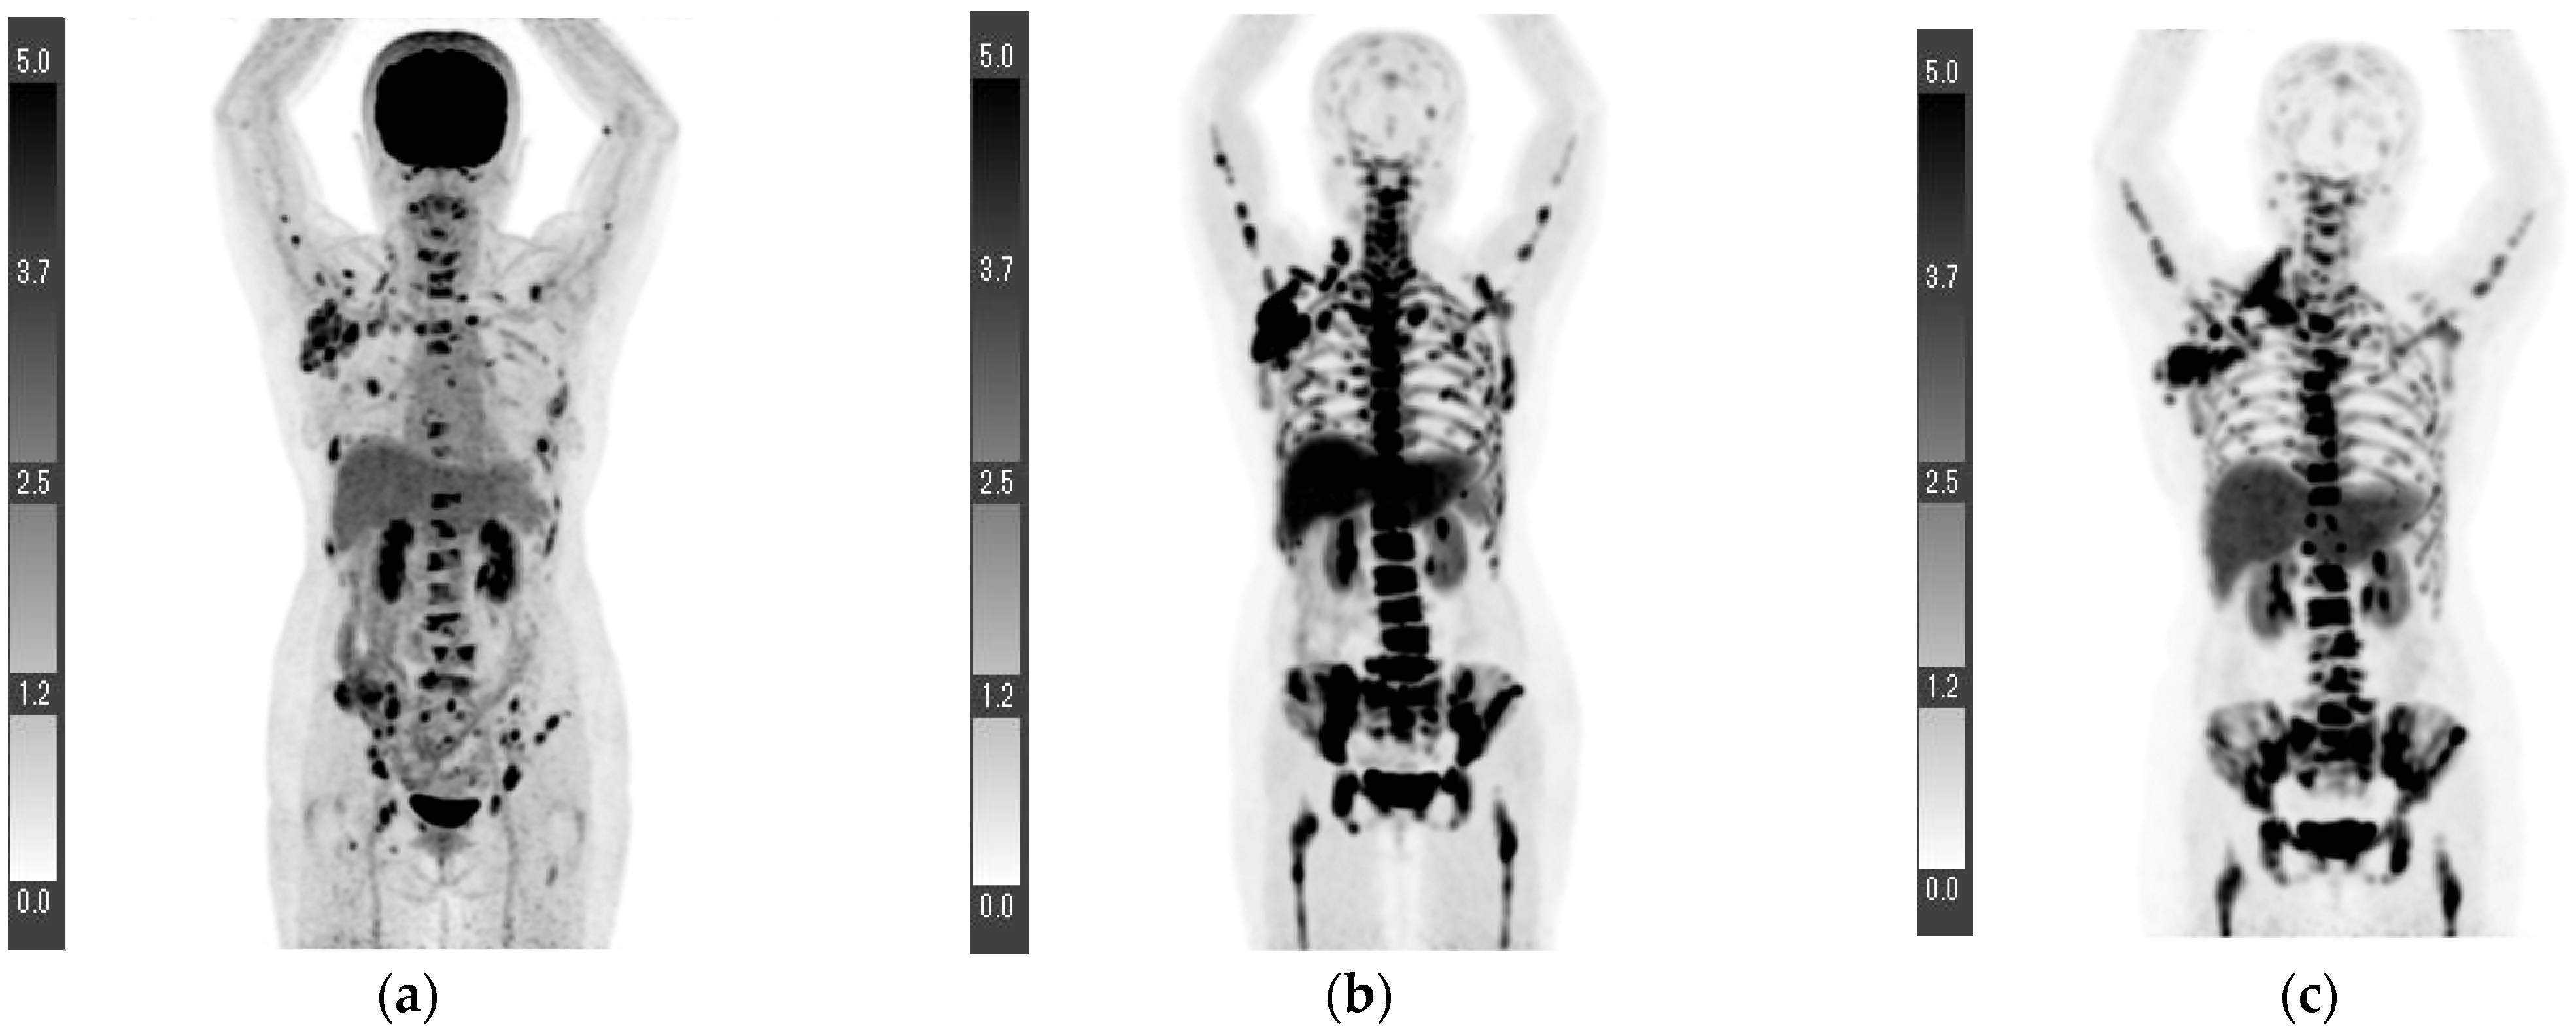

| 4 | 0.4 | 1.5 | 16.7 * | 14.2 * | T1bN3aM1 *** (Lymph node and bone metastases) | Invasive ductal carcinoma | Data loss | + | + | − | Data loss |

| 5 | 3.8 | 8.3 | 1.8 | 6.3 | T2N3bM0 *** | Invasive ductal carcinoma | 1 | + | + | − | 25 |

| 6 | 4.8 | 8.4 | 1.4 | 3.2 | T4bN1M1 *** (Lumbar vertebra metastasis) | Invasive ductal carcinoma | 1 | + | + | − | 8.9 |

| 7 **** | 7.0 | 10.1 | 1.2 | 0.7 | T4bN0M0 | Invasive ductal carcinoma | Data loss | − | − | + | 59 |

| 8 ***** | - | - | 1.1 | 4.1 | N3bM1 (Lymph node, lung, and bone metastases) | Invasive ductal carcinoma | 3 | + | − | + | 29.3 |